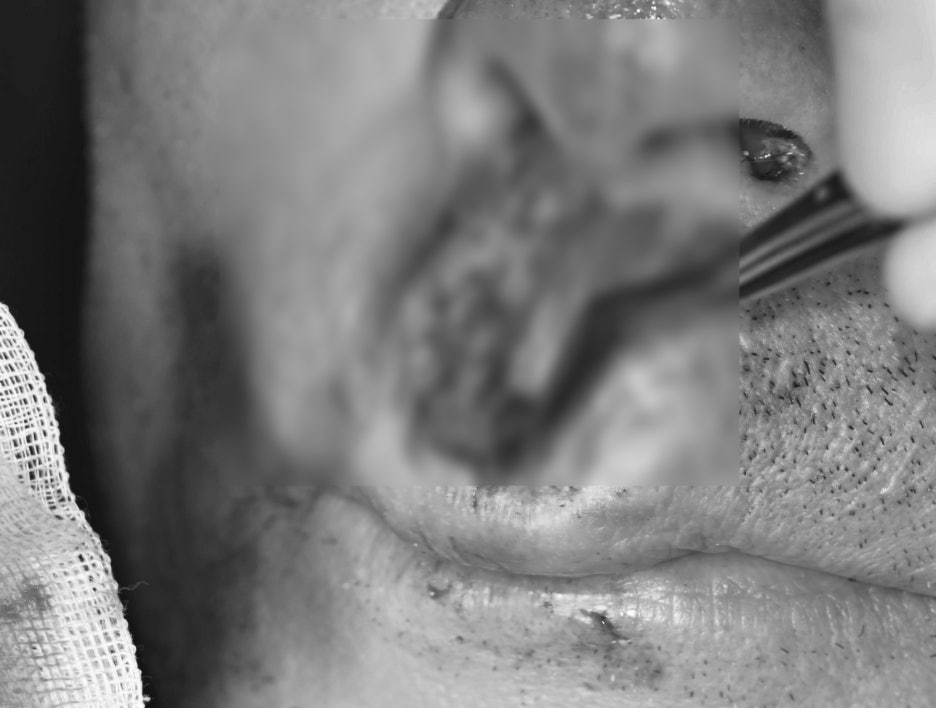

① 응급 열상 봉합술

– 입술과 잇몸이 찢어진 부위를

깨끗하게 소독한 후 봉합했습니다.

– 감염을 예방하기 위해

항생제와 소염제를 병행했습니다.

열상부위 회복 된 사진